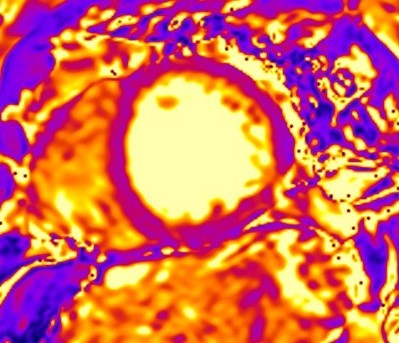

Although LGE is well-established as the technique of choice for the assessment of replacement fibrosis, it cannot evaluate diffuse fibrosis, because it is based on signal intensity differences between scarred and normal myocardium [11]. To overcome this limitation, parametric imaging was developed including T1 mapping (Fig. 8) and extracellular volume fraction (ECV) quantification [11]. T1 mapping (native/pre-contrast and post-contrast after administration of gadolinium-based contrast agent) provides a quantitative assessment of tissue T1 values and enables identification of diffuse myocardial fibrosis [11]. ECV is calculated using native T1 mapping, post-contrast T1 mapping and the patient’s haematocrit, with the latter preferably having been measured on the same day as the CMR study. ECV is calculated based on the following formula:

Fig. 8.

Fig. 8.Detection of microfibrosis using T1 mapping. T1

mapping in patient with polymyositis and ventricular arrhythmias (T1 map = 1400

ms, normal values